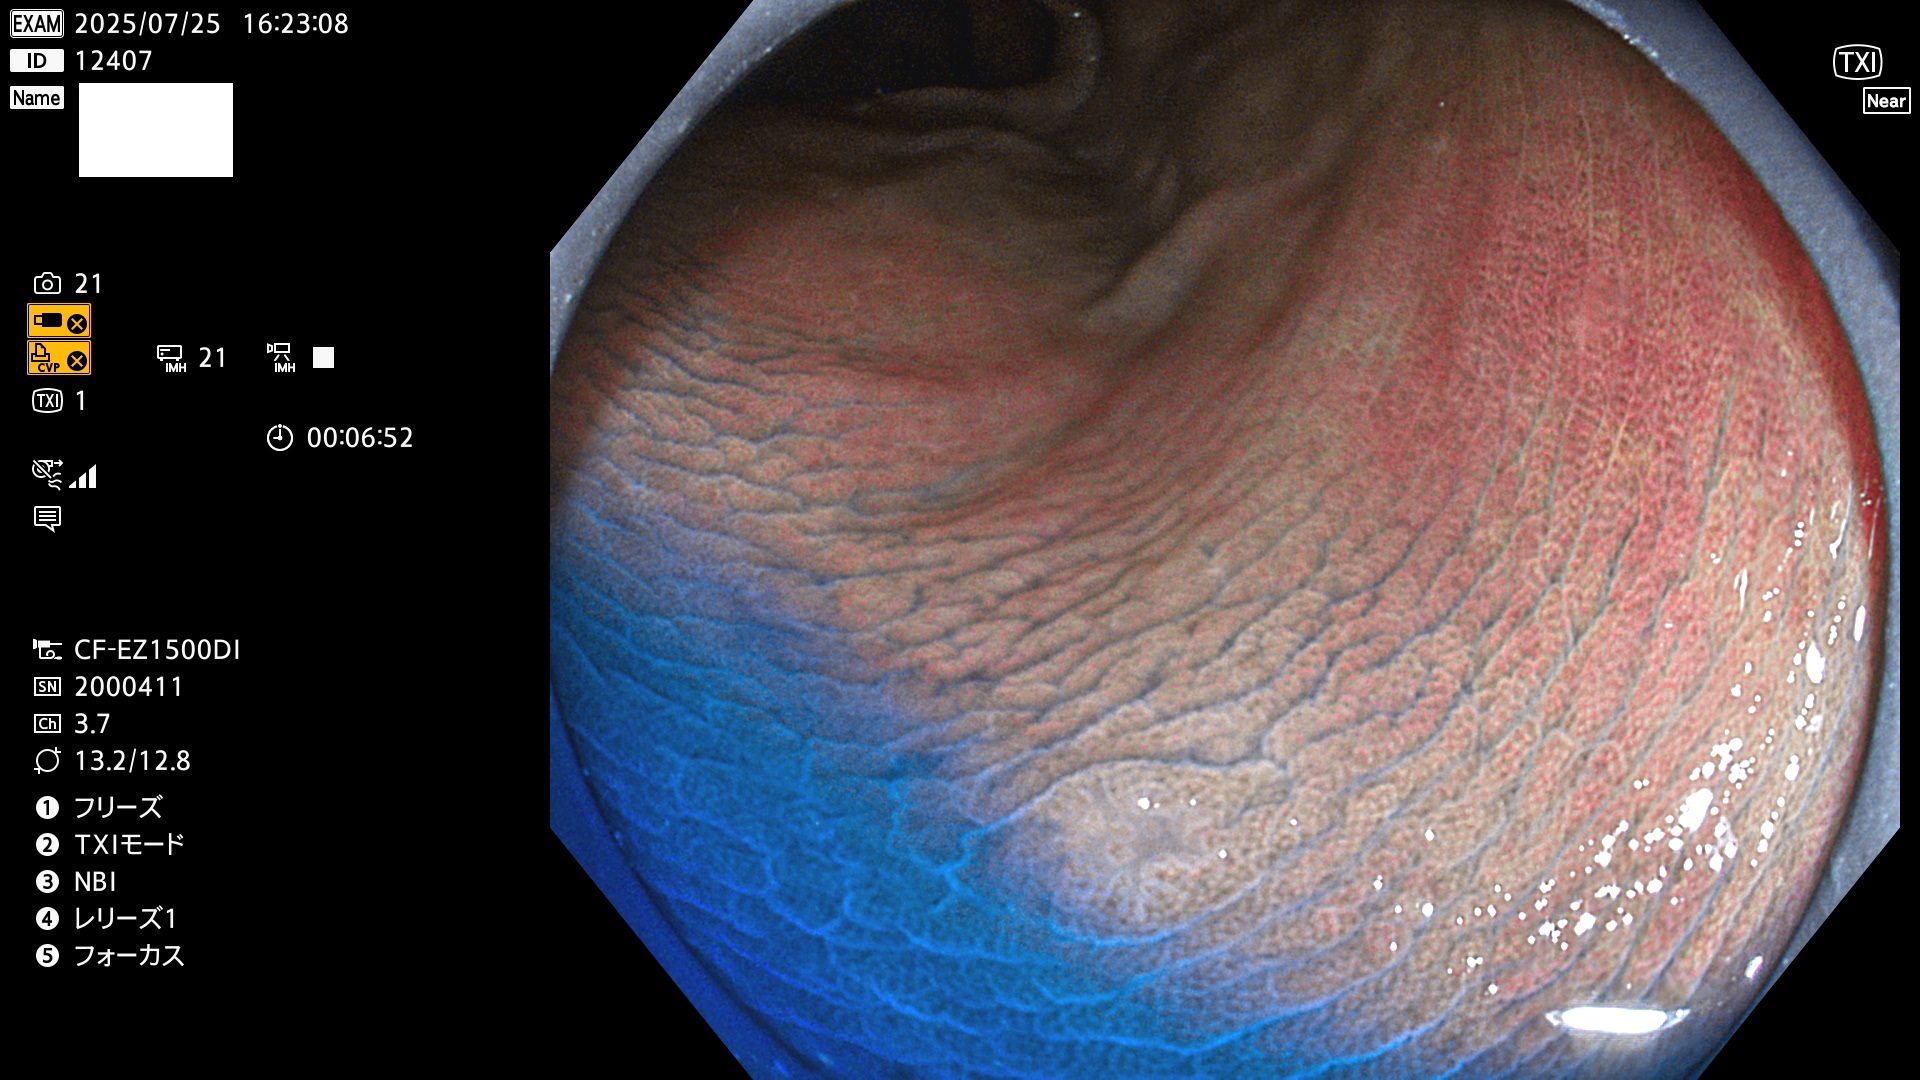

完全に平坦な物をUb、陥凹している物をUcと呼びます。Ubは認識が困難で、Ucはびらん(炎症)と紛らわしいために見落とされやすく、「内視鏡後・大腸癌」の原因になります。

専門的)Uc=De Novo癌? 内視鏡の解像度が低かった時代、このような説もありました。しかし今日の高精度内視鏡では良性の微小なUc型腺腫(APC遺伝子異常の腺腫)が日常的に見つかります。Ucこそが多段階発癌(Adenoma-Carcinoma Sequence)のMain Routeです。

2025年7月24日〜7月27日の4日間(40件)15個 (Uc_ADR=15個/40人=38%)